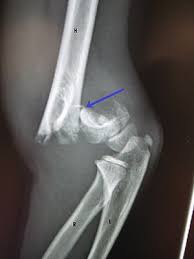

שבר הומרוס בייספס במרפק

שחזור וקיבוע שבר (סגור או פתוח) הומרוס פרוקסימאלי